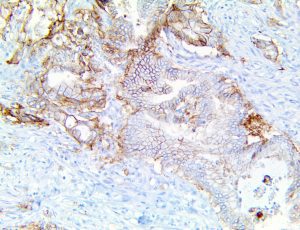

It is the ICU physician who is most likely to witness one of the deadliest manifestations of the abnormal immunological response, the cytokine storm syndrome (CSS). This response is also referred to by some as the cytokine release syndrome (CRS). CSS is characterized by continuous activation and expansion of macrophage and lymphocyte populations, which secrete large amounts of cytokines, causing the cytokine storm. This massive cytokine release is akin to hemophagocytic lymphohistiocytosis (HLH) disease, a syndrome characterized by initial unchecked and persistent activation of cytotoxic T lymphocytes and NK cells.

This activation induces inflammatory monocytes to highly express IL-6, starting a localized and then systemic cascade effect that results in hyperproduction of IL-6, which accelerates the inflammatory process. Because IL-6 also increases vascular permeability, excessive levels cause blood vessels to become very leaky. This, along with clotting factors released from vascular endothelial cells, stimulates the coagulation cascade, resulting in microthrombosis (tiny clots), which leads to ischemia and tissue death of the kidney, intestines, heart, liver, brain and extremities.